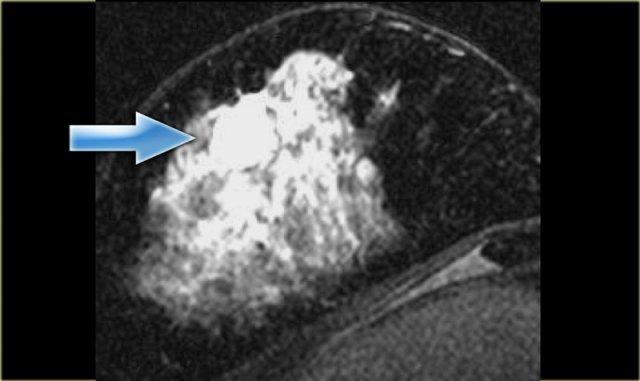

Ngấm thuốc viền ngoại vi

Hình ảnh bên trái cho thấy ngấm thuốc viền ngoại vi của một tổn thương xâm lấn mô xung quanh trong trường hợp ung thư biểu mô ống xâm nhập.